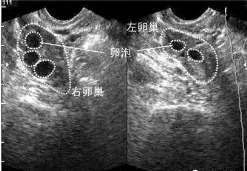

查看全文中部战区总医院全称中国人民解放军中部战区总医院。生殖中心开展了丈夫精子人工授精、常规体外受精-胚胎移植和卵胞浆 […]

查看全文柬埔寨的体外受精进程 下面咱们来具体了解一下柬埔寨的试管婴儿流程。尽管一般的试管婴儿流程和国内是相同的,可是有 […]